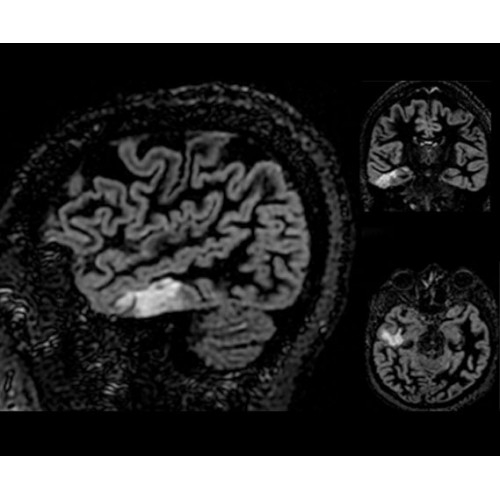

SIGNA PET/MR 3.0T — это гибридная система, в которой совмещаются две принципиально разные технологии — магнитно-резонансную томографию (МРТ) и позитронно-эмиссионную томографию (ПЭТ). Система отличающийся высокой чувствительностью и эффективностью и предназначена для диагностики в области онкологии, неврологии, кардио-васкулярных исследований, исследований воспалительных процессов.

Компания GE Healthcare представляет революционную, полностью интегрированную систему SIGNA PET/MR1, в которой сочетаются времяпролетная технология (TOF) и возможности напряженности магнитного поля 3.0 Тл. Мы поможем вам поднять исследования на более высокий уровень. SIGNA PET/MR позволяет достичь впечатляющей точности и скорости исследований, а благодаря новейшей технологии реконструкции Q.Clear2 качество изображений улучшается в два раза. Кроме того, в систему включен полный набор клинических приложений и гибких катушек для проведения любых видов исследования, открывая для вас возможности визуализации, о которых вы даже не догадывались.

Кроме того, в результате использования технологии TOF и инновационной технологии реконструкции Q.Clear вы сможете добиться прекрасного соотношения сигнал/шум. А благодаря технологии нулевого времени эхо (ZTE) визуализировать костную структуру без ионизирующего излучения. Все эти разработки для улучшения качества сканирования и точности анализа помогут вам использовать весь потенциал ПЭТ/МРТ.